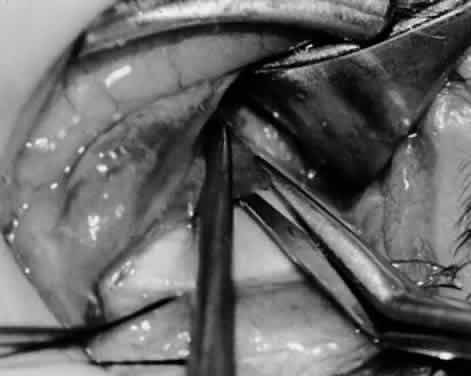

Fig. 11. Sutures are placed into the insertion of the inferior oblique muscle before it is sectioned from the globe for the recession procedure.

Fig. 12. An Aebli scissor is placed beneath the inferior oblique muscle insertion before it is sectioned from the globe.